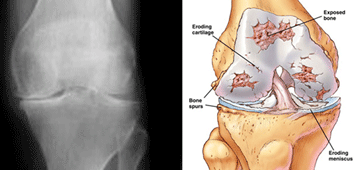

Nëse nuk kryhet operacion çfarë mund të ndodhë?

Normalisht, osteoartriti i gjurit është progresiv dhe ankesat me kalimin e kohës shtohen. Kurse në disa pacientë ankesat janë të ndryshueshme; herë shtohen dhe herë-herë pacienti është i qetë. Nëse artriti i gjurit lihet në mëshirë të fatit nuk mund të pritet që ai të përmirësohet. Lëvizjet e gjurit sa vjen e kufizohen dhe në këtë situatë, për shkak se ecja e pacientit nuk është normale, shkaktohen dhimbje të ekstremiteteve të poshtme dhe të belit, mesit.